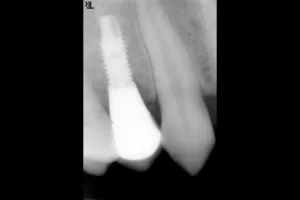

症例①

| 主訴 | 永久歯が生えてこない |

|---|---|

| 診断名 | 後続永久歯欠損 |

| 年齢 | 25歳 |

治療に用いた装置(治療法) | インプラント |

| 部位 | 右上4 |

| 治療期間 | 5か月 |

| 治療費用 | 462,000円 |

| リスク・副作用(治療に関する) | 腫脹、しびれ |